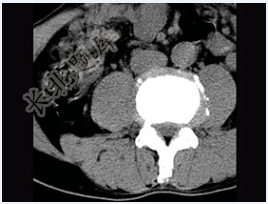

- 单项选择题男,45岁,腰痛,请结合所提供图像,选择最佳答案( )

A、前纵韧带钙化

B、椎间盘膨出

C、椎间盘突出

D、腰椎骨质增生

E、椎间盘未见异常